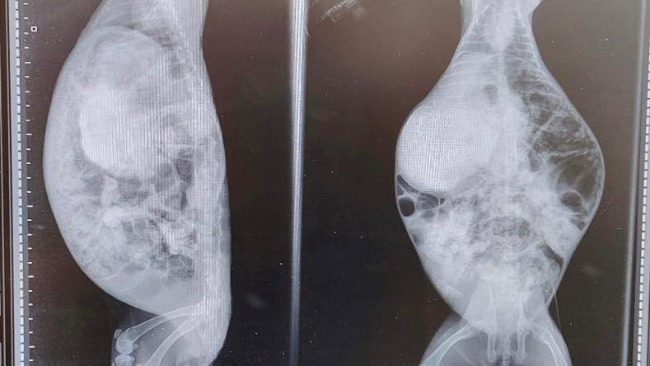

Rozpoczęliśmy więc diagnostykę. Poniżej przykładowe wymazy naszych podopiecznych:

Takie przypadłości jak EC, pasteurella, bordetella i inne bakterie były u nich na porządku dziennym. W niektórych przypadkach badania krwi ujawniły również EC.